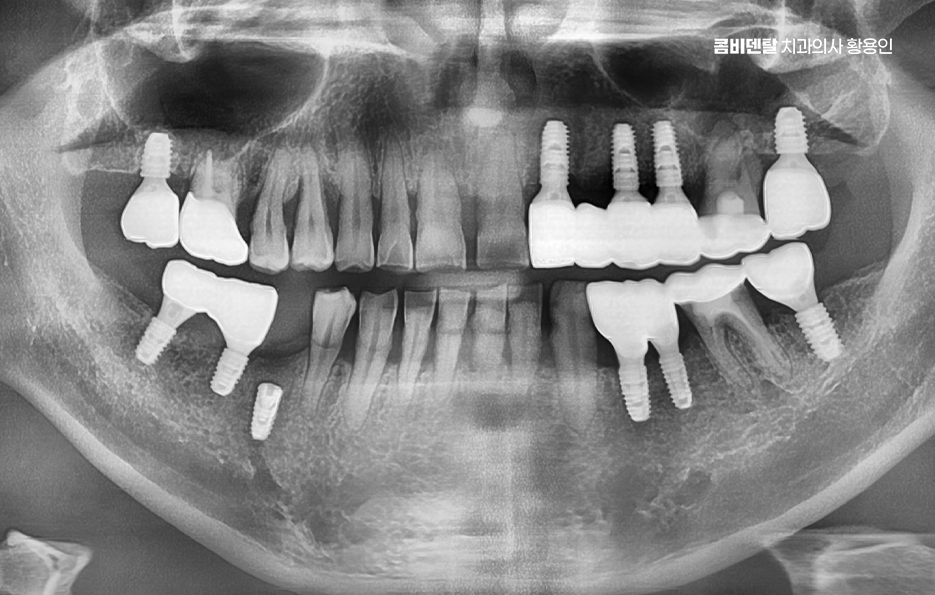

발치를 한 후에 아무 치료 없이 방치하게 되면 여러 문제가 연쇄적으로 생기는데 우선 그 자리에 음식물이 끼기 쉽고, 옆에 있는 치아가 빈 공간 쪽으로 기울어지게 되며 시간이 지나면 맞물리는 치아도 내려오거나 올라오면서 전체 교합이 틀어지게 되는데 이게 단순히 치열 문제만이 아니라 씹는 힘의 불균형을 만들면서 턱관절에 무리를 줄 수 있어요.

또 치아가 없어진 자리는 잇몸 뼈가 점점 흡수되면서 꺼지게 되는데, 그 결과 얼굴이 비대칭으로 보이거나 추후에는 임플란트를 하려고 해도 부족한 잇몸 뼈로 인해 뼈이식과 같은 치료를 추가적으로 받아야 할 수 있었어요

치아 발치 후 임플란트 치료 과정은 처음에 CT나 파노라마 엑스레이를 통해 뼈의 양과 밀도, 신경 위치를 정확히 확인하는 것부터 시작되며 치아가 빠진 자리에 뼈가 많이 흡수되어 있다면, 임플란트를 심기 전에 뼈이식을 먼저 해야 할 수 있지만 반대로 뼈 상태가 좋다면 임플란트를 심고, 보통 3개월 동안 뼈와 잘 붙을 때까지 골융합 과정을 기다리게 되며 골융합이 잘 이루어진 뒤에는 그 위에 지대주라는 연결 부품을 끼우고, 그 위에 최종 보철물을 씌우면서 치료가 마무리되고 있어요

치아 발치 후 임플란트 치료 과정을 안정적으로 잘 진행하는 것도 중요하지만 임플란트가 아무 문제 없이 계속 유지되는 건 아니며 시술 후 관리가 제대로 되지 않으면 ‘임플란트 주위염’이라는 염증이 생길 수 있었어요.

이는 잇몸질환처럼 보이지만, 임플란트 주변 뼈까지 녹아내리게 만들기 때문에 치명적일 수 있는데 이러한 부작용을 잘 예방하려면 정기적으로 치과에서 검진을 받고, 올바른 양치 습관과 위생 관리를 철저히 해야 하는 것이며 특히 임플란트는 신경이 없기 때문에 염증이 생겨도 통증이 늦게 나타나는 경우가 많아서 통증이 없더라도 정기적인 관리를 소홀히 하면 안 되고 사후관리까지 잘 고려한 치과 선택이 중요한 거예요